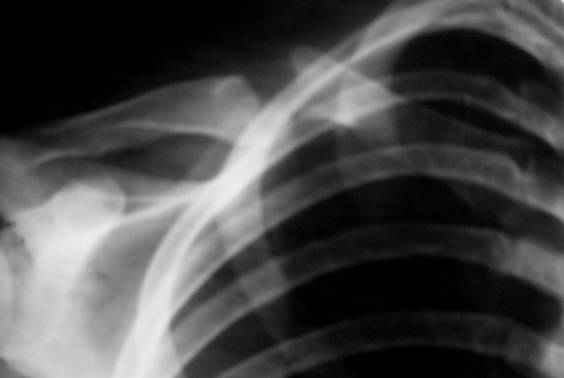

Ложный сустав ключицы

Уважаемые коллеги! Прошу дать совет о вариантах лечения ложного сустава ключицы.

Больная 17 лет, кандидат в мастера спорта по легкой атлетике. Перелом ключицы в 14 лет. Последнее время появилась боль в области несращения. Предполагал сделать костную аутопластику (из гребня подвздошной кости) с фиксацией реконструктивной пластиной с 5 отверстиями. Сомнения - год назад делал подобную операцию, сращения не наступило. Причина - не знаю. Больной надо в короткие сроки ( соревнования) восстановиться. Что сделать?